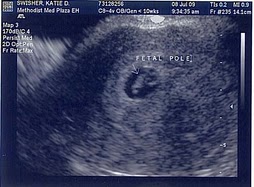

One of two pictures taken during Henry’s birth. The other was during the surgery, and a nurse stepped right in front of Matt when he was taking the picture. Sorry Henry. Your sister has about a hundred photos of her birth, but this is all you got.